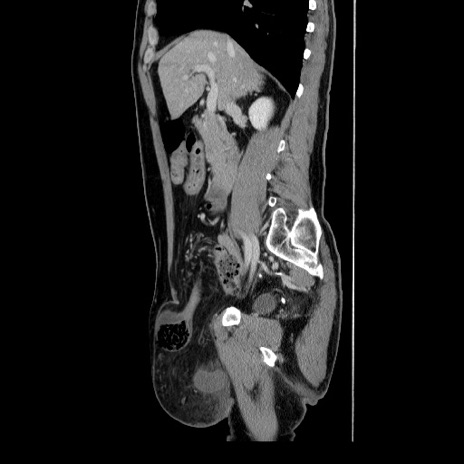

症例34(矢状断像)

【症例】60歳代 男性

【主訴】右鼠径部膨隆

【現病歴】1年程前より右鼠径部膨隆あり。自己にて還納可能だったため放置していた。3時間前より右鼠径部の脱出を認め、還納困難となり受診。

【身体所見】右鼠径部に小児頭大の膨隆あり。弾性硬であり、用手還納は困難。左鼠径部にも膨隆を認める。脱出はなし。